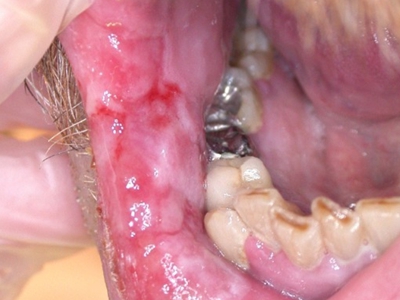

二期口腔梅毒会出现梅毒性黏膜炎及梅毒黏膜斑症状,梅毒性黏膜炎好发于舌、唇黏膜及口角等处,表现为黏膜充血、弥漫性潮红,可有糜烂。舌背有大小不一的光滑区,舌乳头消失。

梅毒黏膜斑是二期梅毒最常见的口腔损害。可发生在口腔黏膜的任何部位,以唇黏膜最多见,其次为软腭、舌背、舌底等部位。损害呈灰白色、光亮而微隆的斑块,圆形或椭圆形,直径约1cm,边界清楚。易发生糜烂或浅表溃疡,表面覆盖灰白色假膜,周围有红晕。黏膜斑常为多个,内含有大量梅毒螺旋体。